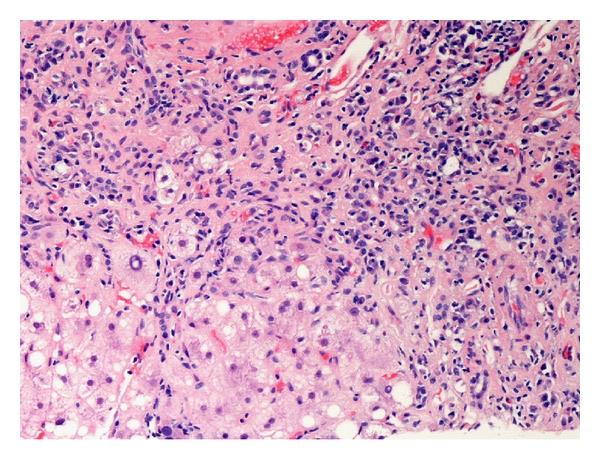

Autoimmune hepatitis (AIH) is a chronic inflammatory disorder characterized by periportal inflammation, elevated immunoglobulins, autoantibodies, and a dramatic response to immunosuppression. An environmental agent is hypothesized to trigger an immune-mediated attack directed against liver antigens in genetically predisposed individuals. A plethora of clinical presentations can be seen ranging from chronic indolent disease to fulminant hepatic failure, and diagnosis requires exclusion of other causes of liver disease. Corticosteroid therapy must be instituted early and modified in an individualized fashion. Treatment decisions are often complicated by the diverse clinical manifestations, uncertainty about natural history, evolving ideas about treatment end points, and a multitude of alternative immunosuppressive agents. Achieving normal liver tests and tissue is the ideal treatment end point, but needs to be weighed against the risk of side effects. Decompensated patients may benefit from early liver transplantation. Long-term prognosis is excellent with early and aggressive initiation of therapy. Our paper discusses AIH, giving a detailed overview of its clinical presentation, risk factors, immunopathogenesis, up-to-date diagnostic criteria, current updates in therapy with a brief discussion of AIH in pregnancy, and long-term implications for cirrhosis and hepatocellular carcinoma in AIH patients.

自身免疫性肝炎(AIH)是一种慢性炎症性疾病,其特征为汇管区周围炎症、免疫球蛋白升高、自身抗体以及对免疫抑制有显著反应。据推测,环境因素会在遗传易感性个体中引发针对肝脏抗原的免疫介导攻击。AIH有多种临床表现,从慢性隐匿性疾病到暴发性肝衰竭不等,诊断需要排除其他肝病病因。必须尽早开始使用皮质类固醇疗法,并根据个体情况进行调整。治疗决策常常因临床表现多样、自然病史不确定、治疗终点观念不断演变以及多种替代免疫抑制剂而变得复杂。实现肝功能检查和组织正常是理想的治疗终点,但需要权衡副作用风险。失代偿患者可能从早期肝移植中获益。早期积极开始治疗,长期预后良好。我们的论文讨论了AIH,详细概述了其临床表现、危险因素、免疫发病机制、最新诊断标准、当前治疗进展,并简要讨论了妊娠合并AIH以及AIH患者发生肝硬化和肝细胞癌的长期影响。